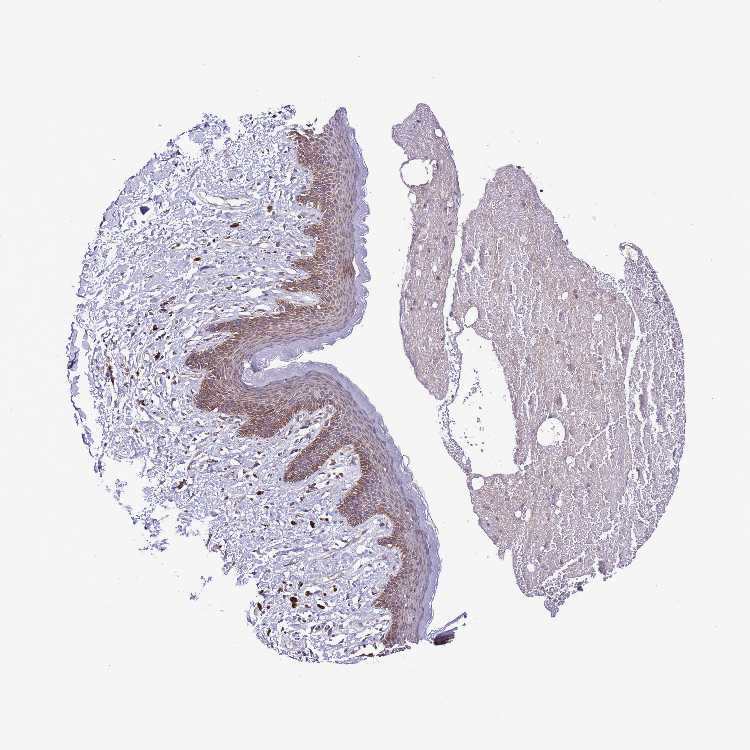

SKIN 1 - Antibody stainingi

Antibody staining in the annotated cell types in the current human tissue is reported as not detected, low, medium, or high, based on conventional immunohistochemistry profiling in selected tissues. This score is based on the combination of the staining intensity and fraction of stained cells.

Each image is clickable and will lead to virtual microscopy that enables deeper exploration of all samples and also displays staining intensity scores, fraction scores and subcellular localization as well as patient and tissue information for each sample.

Antibody HPA046684

Langerhans Not detected

Fibroblasts Not detected

Keratinocytes Medium

Melanocytes Medium

SKIN 2 - Antibody stainingi

Epidermal cells Medium